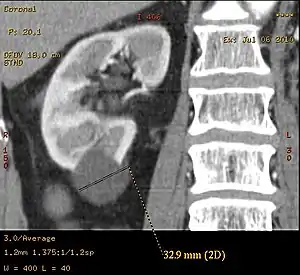

![]() | |

| Renal cyst of the left kidney (hyperintense area) as shown on MRI. | |